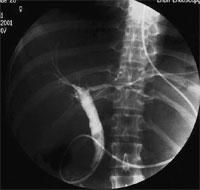

內鏡逆行胰膽管造影

內鏡逆行胰膽管造影(endoscopicretrogradecholangiopancreatography,ERCP)患者口服膽囊造影劑多不顯影,ERCP作為直接膽道造影的方法之一,是頗具診斷價值的檢查方法。文獻認為ERCP表現為:

(1)肝總管處可見邊緣光滑的圓形充盈缺損影,有人稱之為“反C征”,此充盈缺損以上的肝總管及肝內膽管顯著擴張,缺損以下的膽總管輕度擴張或正常,偶見肝總管被牽拉移位與膽總管形成“<”狀,是因為膽囊向心性萎縮所致。

(2)本徵Ⅰ型肝內外膽管輕到中度擴張,Ⅱ、Ⅲ型中到重度擴張,以肝總管及肝內膽管擴張為著,完全梗阻者上段不顯影。

(3)膽囊萎縮,有部分患者膽囊不顯影,膽囊管明顯擴張伴結石影,膽囊膽管之間出現交通陰影時,表示有內瘺存在。

(4)部分患者合併膽總管結石。

(5)部分患者膽總管下端炎性狹窄或結石梗阻致排空不暢,膽管不顯影或顯影不良。